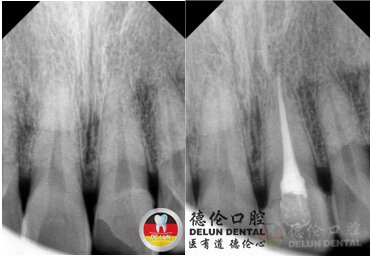

罗朝阳医生牙髓病治疗案例

德伦口腔罗朝阳医生:目前牙髓炎好的治疗方式是进行微创根管治疗,用专用的器械通过彻底减少感染的牙髓以及感染的牙本质和毒性分解产物,以减少根管内容物对根尖周围组织的不良刺激,并适当的消毒,严密填塞根管,隔绝细菌进入根管再次感染。

我们德伦口腔现采用德国leica光纤超显微内窥镜,进行微创根管治疗,这种德国设备以及其精细的探头尺寸(小至0.06 mm),发现病灶,解决病灶。同时这个设备还具备高清3D立体投影效果,避免软组织损伤,手术减少了手术后的肿胀不适,恢复更快。